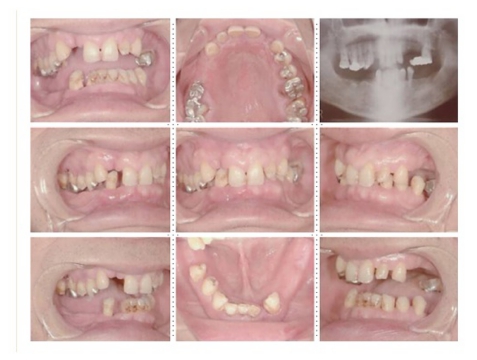

症例1

58才 女性

嘔吐反応が激しく入れ歯を入れると気持ち悪くなってしまうと、インプラント希望で来院されました。

上顎左右奥に4本ずつ計8本のインプラント埋入。下顎左右奥に3本ずつ計6本のインプラント埋入上下顎とも全体的にセラミックを使用した冠をセット。